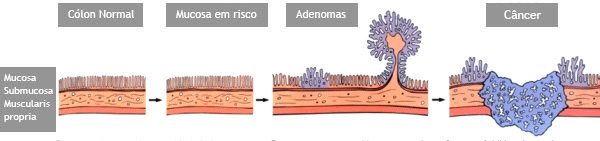

Colonoscopia é o exame endoscópico do cólon (intestino grosso) e muitas vezes também do íleo terminal (porção final do intestino delgado). Além da inspeção da superfície intestinal, a colonoscopia permite também a realização de biópsias que podem ser úteis no estabelecimento do diagnóstico. Procedimentos terapêuticos também podem ser realizados durante a colonoscopia, entre eles o mais frequente é a remoção de pólipos (polipectomia).

- Prevenção e detecção precoce do câncer de cólon. A colonoscopia pode ajudar a encontrar pólipos, que podem se tornar câncer. Os pólipos podem ser removidos através de polipectomia. O exame também pode permitir que seu médico encontre tumores cancerosos precocemente, quando é mais fácil de ser curado.

- Se você tem mais de 50 anos de idade, deve fazer uma colonoscopia. Se tiver pais ou irmãos que tiveram câncer no cólon, especialmente antes que eles tivessem 50 anos de idade, você pode ter um maior risco de pólipos ou câncer. Neste caso, o seu médico pode querer começar a triagem antes de você ter 50 anos.

O que são pólipos?

Pólipos são crescimentos na parede interna do tubo digestivo em órgãos como o esôfago, estômago, duodeno e cólon. O cólon e o reto são partes do intestino grosso.

Por que devem ser removidos?

Se não forem removidos cedo, alguns pólipos podem se tornar cancerosos. Se pólipos cancerosos não são tratados, eles são uma ameaça à vida. Porém mesmo sendo canceroso, se for ressecado precocemente e se este não estiver muito infiltrado, a simples retirada do pólipo pode resolver o problema.

Por que apenas a biópsia de um pólipo não é suficiente?

Geralmente apenas uma região do pólipo é que se apresenta de forma cancerosa. Se for realizada uma simples biópsia do pólipo, a região cancerosa pode não ser atingida e o diagnóstico de câncer não ser realizado. Para se ter certeza do diagnóstico, o pólipo inteiro deve ser removido através do procedimento chamado de polipectomia.